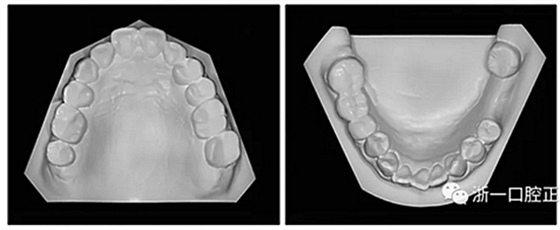

36歲;女性;尋求下頜左后方區(qū)域間隙管理的建議(圖1和圖2),通過治療獲得了良好的牙頜面效果(圖3和圖4)。她被診斷患有骨性I類和代償性牙性II類錯合畸形,并且上頜左側尖牙缺失(圖1和2)。大約七年前,由于不可修復的齲齒,拔除了下頜左側第一和第二磨牙(圖5)。37相鄰的第三磨牙向近中移動并傾斜入間隙,導致無牙頜間隙減小至約14 mm(圖2和圖5)。臨床和影像學評估顯示多發(fā)性齲損和在下頜右側567處有一不良的固定橋修復體(圖1和5)。此外,下頜左中切牙缺失,造成下頜中線向左側偏移約3 mm(圖1和圖2)?;颊咦栽V,她的右上第一前磨牙和左上尖牙在13歲時由其家庭牙醫(yī)拔除,因為它們被阻塞到頰側萌出(圖1)。上頜第二磨牙缺失(未知病因),并且相鄰的第三磨牙已經(jīng)轉移到第二磨牙間隙中。如補充材料所示,美國正畸學差異指數(shù)DI是28分。種植體部位(下頜左側和右側第一磨牙)由于復雜性得到額外4分(補充材料)。

圖2. 治療前牙齒模型